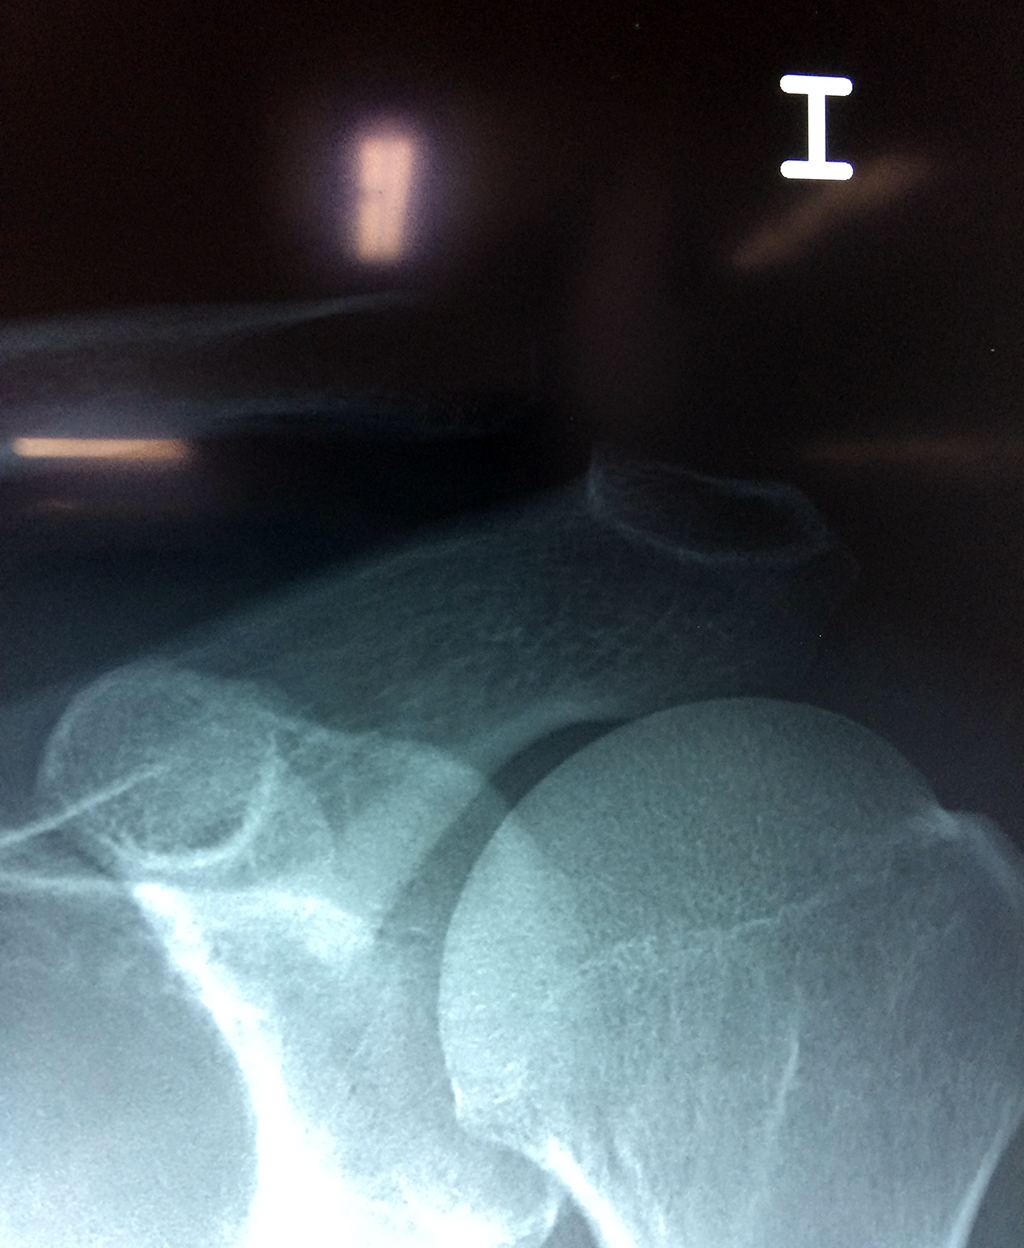

Cirugía de Fémur - Clavícula

La clavícula es un hueso largo, con forma de "S" itálica, situado en la parte anterosuperior del tórax. Junto con la escápula forman la cintura escapular. Se puede palpar por toda su longitud y se extiende del esternón al acromion de la escápula, siguiendo una dirección oblicua lateral y posterior.

Se considera el único medio de unión entre el miembro superior y el tórax. A pesar de su aspecto, similar al de un hueso largo, posee una estructura semejante a la de un hueso plano, ya que carece de epífisis y de diáfisis, lo que la harían entrar dentro de la clasificación de hueso largo. Carece de un canal medular propiamente dicho.